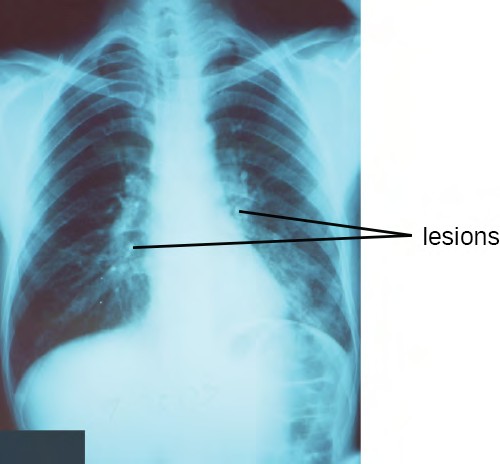

Pneumonia is a general term for infections of the lungs that lead to inflammation and accumulation of fluids and white blood cells in the alveoli. Pneumonia can be caused by bacteria, viruses, fungi, and other organisms, although the vast majority of pneumonias are bacterial in origin. Bacterial pneumonia is a prevalent, potentially serious infection; it caused more 50,000 deaths in the United States in 2014.[6] As the alveoli fill with fluids and white blood cells (consolidation), air exchange becomes impaired and patients experience respiratory distress (Figure 22.9). In addition, pneumonia can lead to pleurisy, an infection of the pleural membrane surrounding the lungs, which can make breathing very painful. Although many different bacteria can cause pneumonia under the right circumstances, three bacterial species cause most clinical cases: Streptococcus pneumoniae, H. influenzae, and Mycoplasma pneumoniae. In addition to these, we will also examine some of the less common causes of pneumonia.

Figure 22.9 A chest radiograph of a patient with pneumonia shows the consolidations (lesions) present as opaque patches. (credit: modification of work by Centers for Disease Control and Prevention)